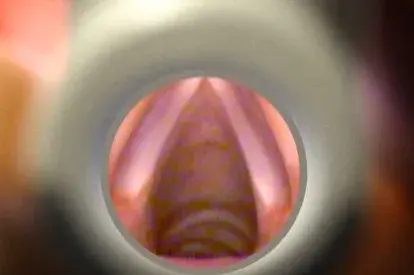

El nuevo diseño HyfinVent® Seal Pecho proporciona 3 canales que impiden el flujo de aire en la cavidad torácica durante la inspiración al tiempo que permite que el aire escape a través de los canales de ventilación.

El nuevo diseño proporciona 3 canales que impiden el flujo de aire en la cavidad torácica durante la inspiración al tiempo que permite que el aire escape a través de los canales de ventilación durante la exhalación . Estos, permiten que la sangre se escape y garantiza la no oclusión, ya que incluso si dos de los tres canales se obstruyen, la ventilación se mantendrá en pleno funcionamiento por el tercer canal.